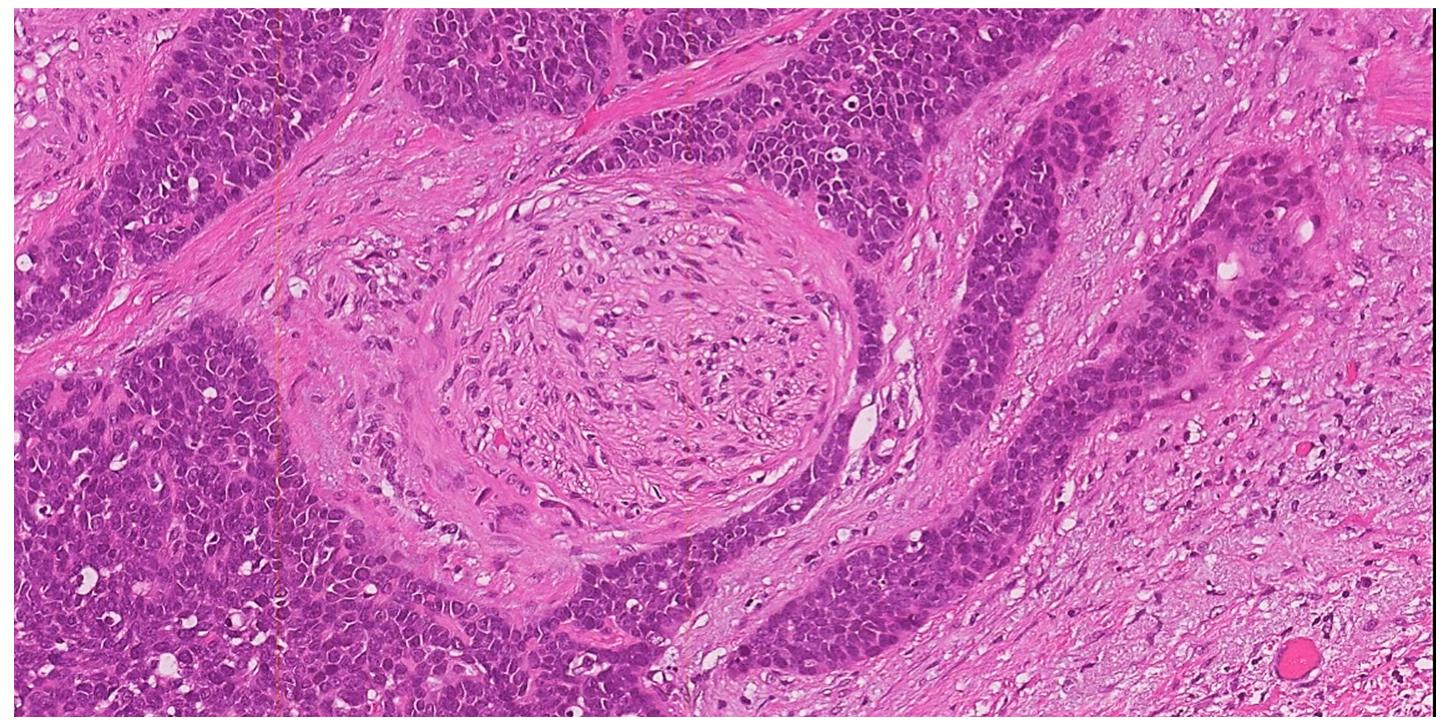

3.2.1. Squamous Cell Carcinoma

- the grading of invasive tumor front or the pattern-type of invasion (pushing versus infiltrative);

3.3. Silva Pattern of Invasion for HPV-Associated Adenocarcinomas